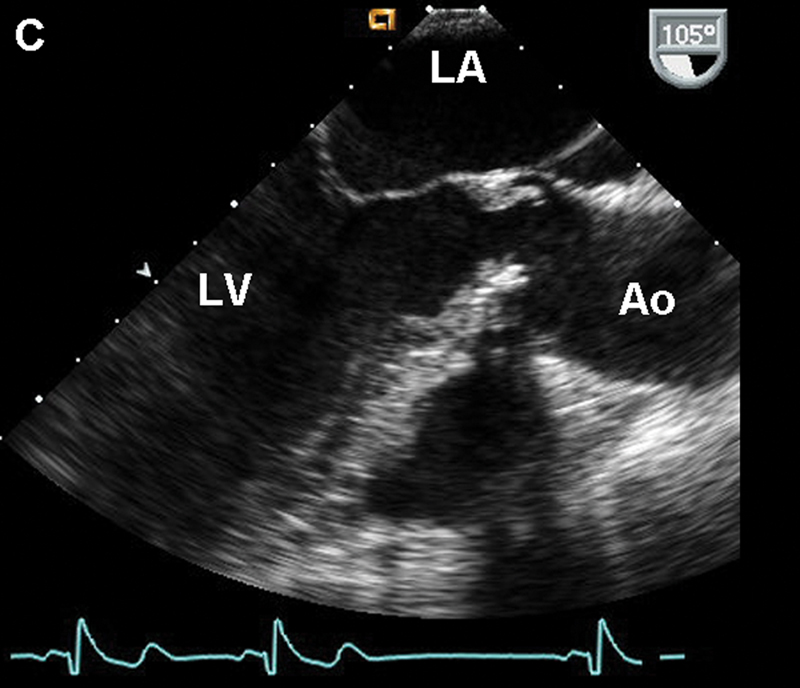

فحوصات تشخيصية لبعض امراض القلب والشرايين التاجية